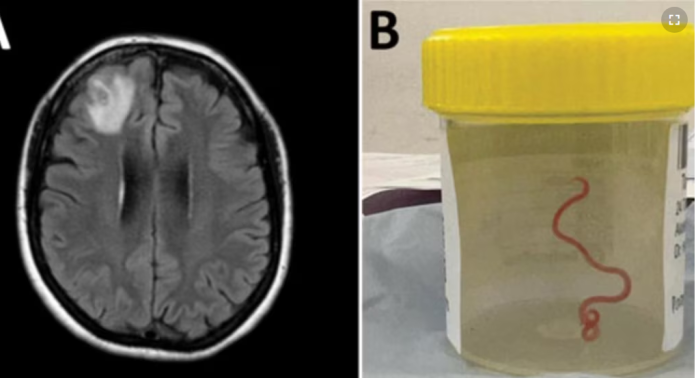

Un gusano de 8 centímetros fue encontrado vivo en el cerebro de una mujer en Australia, y los investigadores dicen que es la primera vez que se descubre este parásito en humanos.

Sídney (VOA) – Un gusano vivo fue extraído del cerebro de una paciente durante una cirugía en la capital australiana, Canberra, en junio de 2022, un extraordinario caso que ha sido documentado en la última edición de la revista Emerging Infectious Diseases.

El gusano rojo, de 8 centímetros de largo, estaba vivo y retorciéndose cuando lo extrajeron del cerebro de la paciente. Los científicos creen que podría haber estado allí desde dos meses antes de ser extraído.

“Ella y todos los que estaban en el quirófano sufrieron el shock de su vida cuando tomó unos fórceps para detectar una anomalía y la anomalía resultó ser un gusano vivo de color rojo claro de 8 centímetros que se retorcía”, dijo. “Incluso si se elimina el factor de repugnancia, se trata de una nueva infección nunca antes documentada en un ser humano”.

En junio de 2022, se sometió a una biopsia en el Hospital de Canberra y se encontró el parásito.